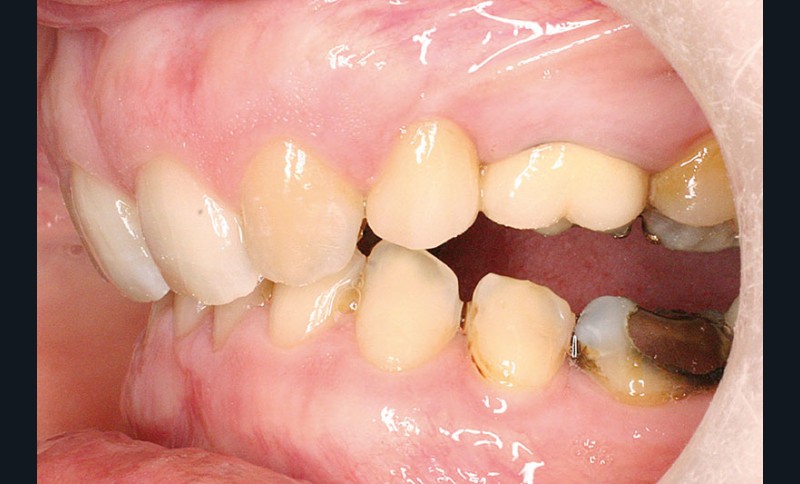

La patiente, âgée de 30 ans, présente des agénésies multiples : 12, 22, 14, 15, 24, 25, 35 et 45 (fig. 1 à 3).

Un traitement orthodontique a déjà été effectué pendant son adolescence avec un choix de fermeture d’espaces qui a entraîné une linguoversion incisive maxillaire excessive (fig. 10), avec un préjudice esthétique important notamment sur le sourire (fig. 11 à 13).